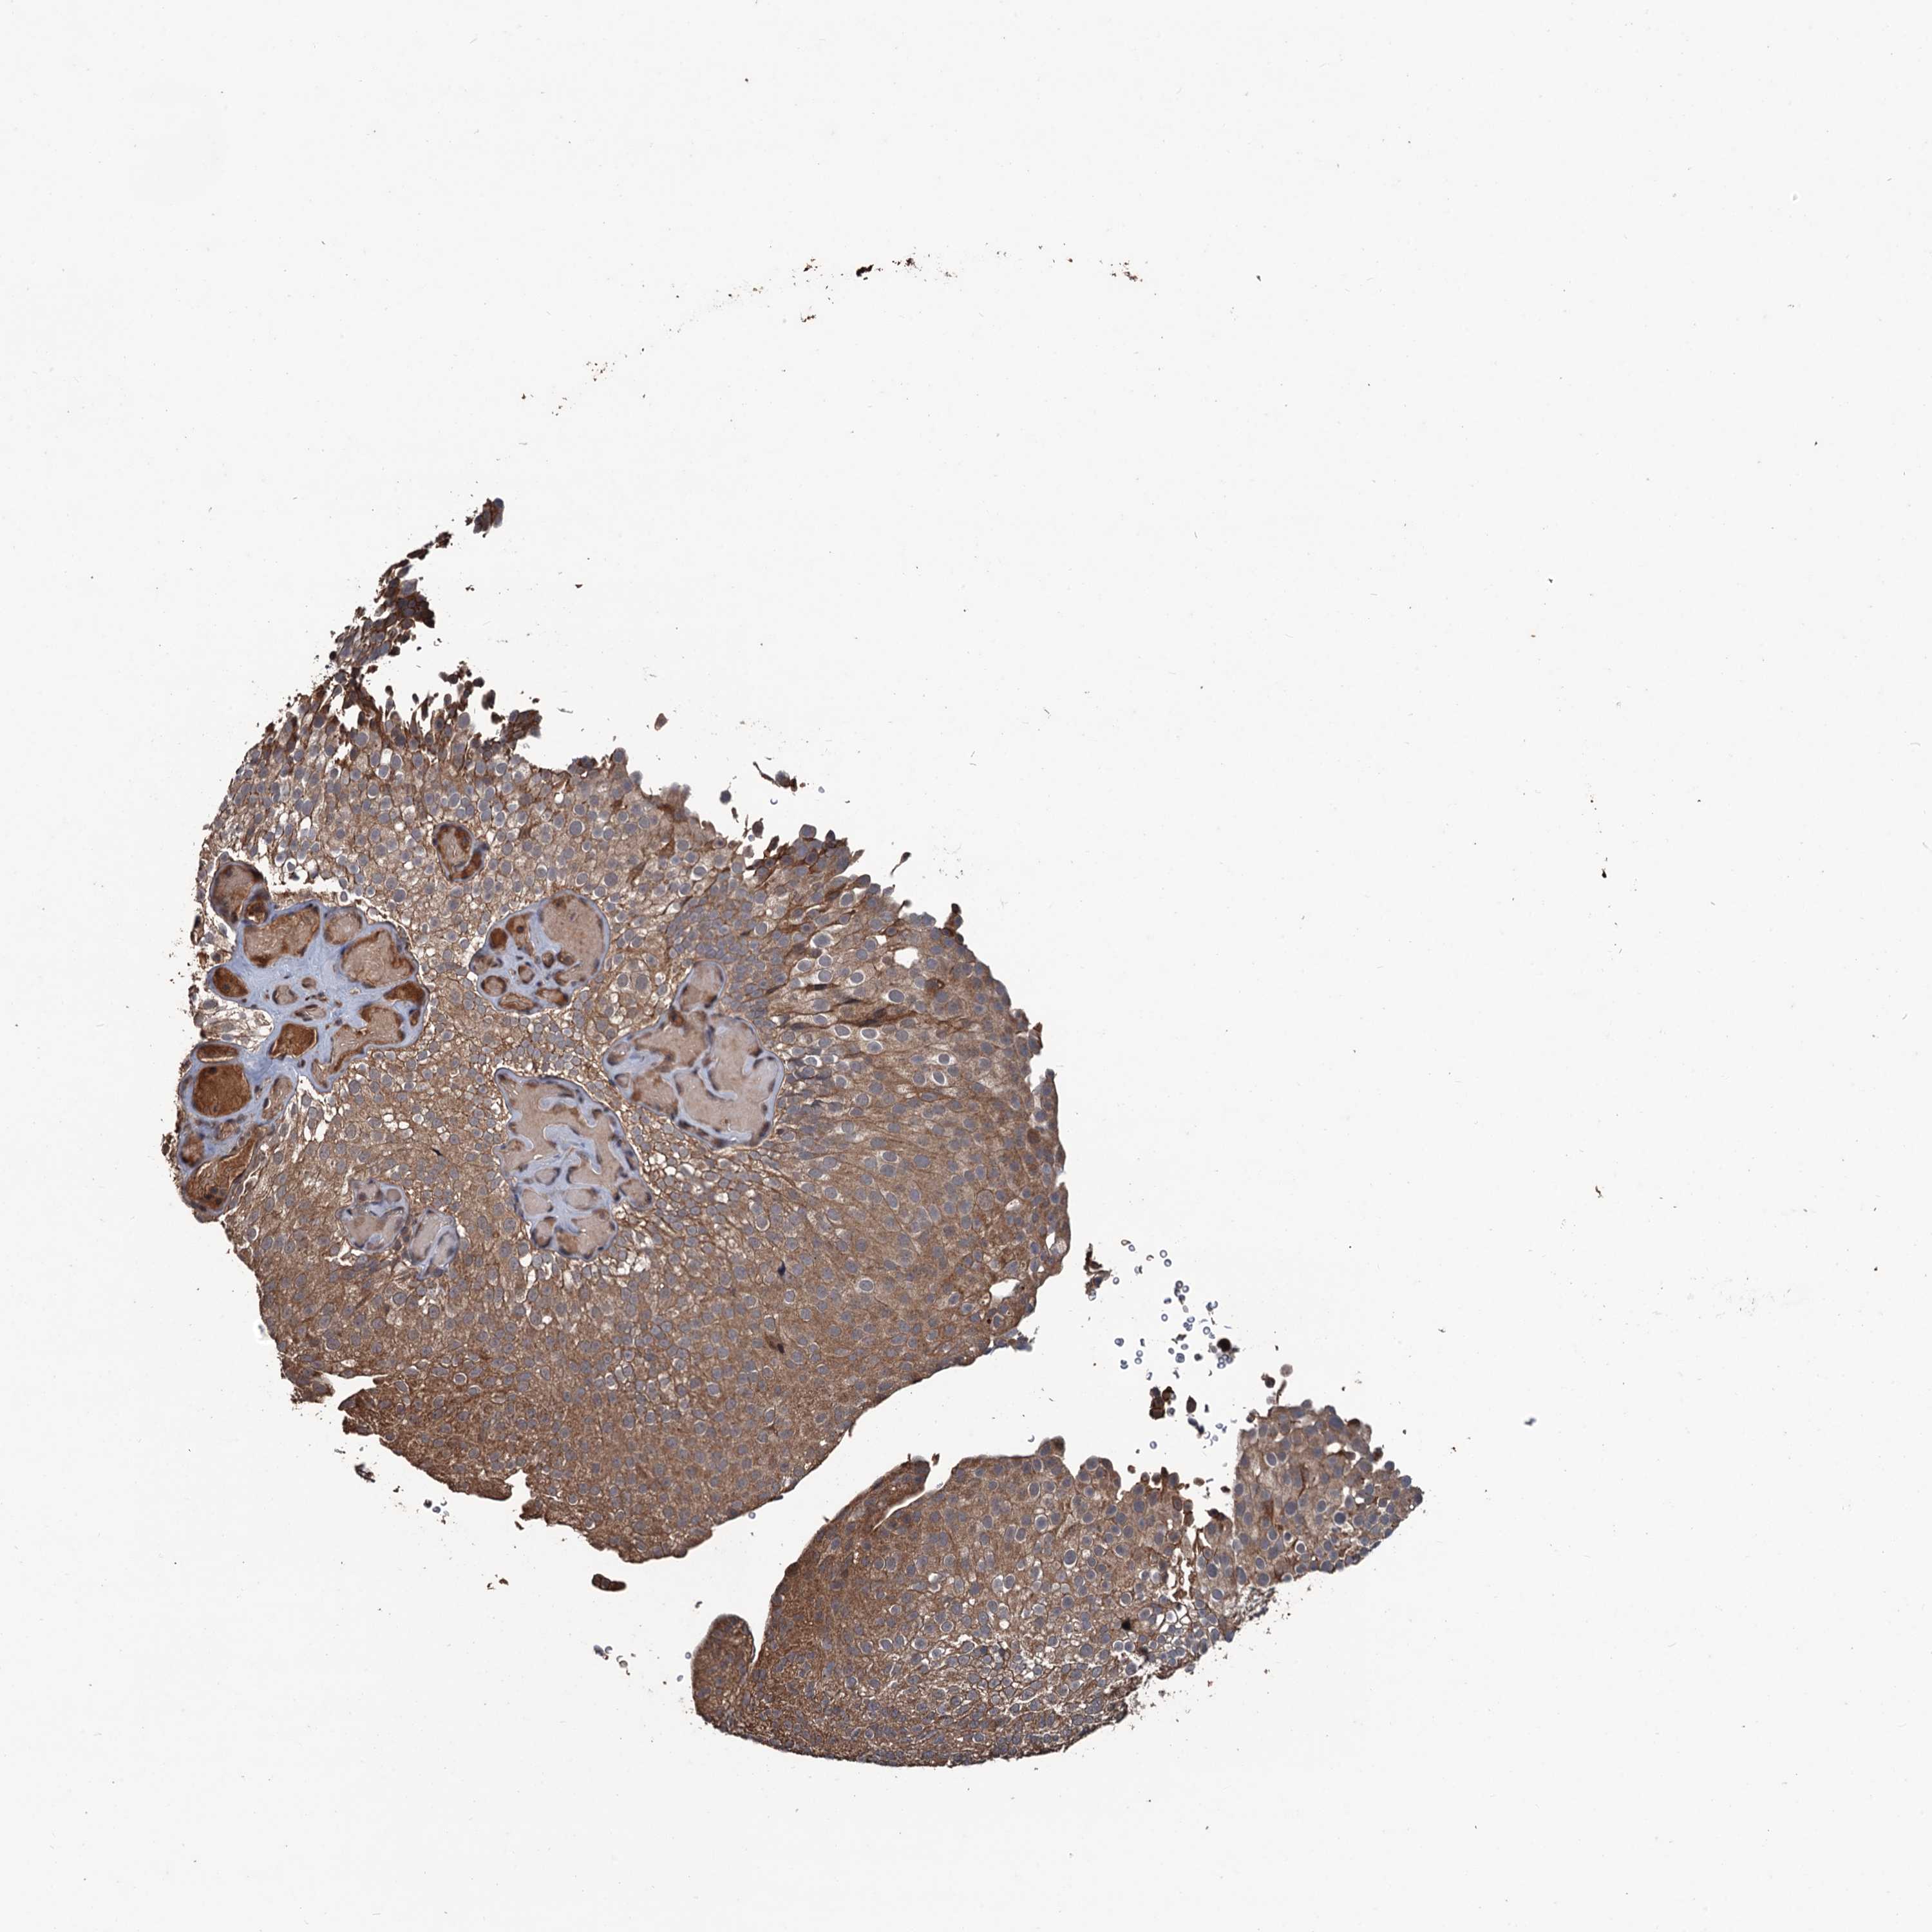

UROTHELIAL CANCER - Protein expressioni

A mouse-over function shows sample information and annotation data. Click on an image to view it in a full screen mode. Samples can be filtered based on level of antibody staining by selecting one or several of the following categories: high, medium, low and not detected. The assay and annotation is described here.

Note that samples used for immunohistochemistry by the Human Protein Atlas do not correspond to samples in the TCGA dataset.

Antibody stainingi

Antibody staining in the annotated cell types in the current human tissue is reported as not detected, low, medium, or high, based on conventional immunohistochemistry profiling in selected tissues. This score is based on the combination of the staining intensity and fraction of stained cells.

Each image is clickable and will lead to virtual microscopy that enables deeper exploration of all samples and also displays staining intensity scores, fraction scores and subcellular localization as well as patient and tissue information for each sample.

Antibody HPA039843

Staining

High

Medium

Low

Not detected

Intensity

Strong

Moderate

Weak

Negative

Quantity

>75%

75%-25%

<25%

None

Location

Nuclear

Cytoplasmic/membranous

Cytoplasmic/membranous,nuclear

Urothelial carcinoma, High grade

Urothelial carcinoma, Low grade